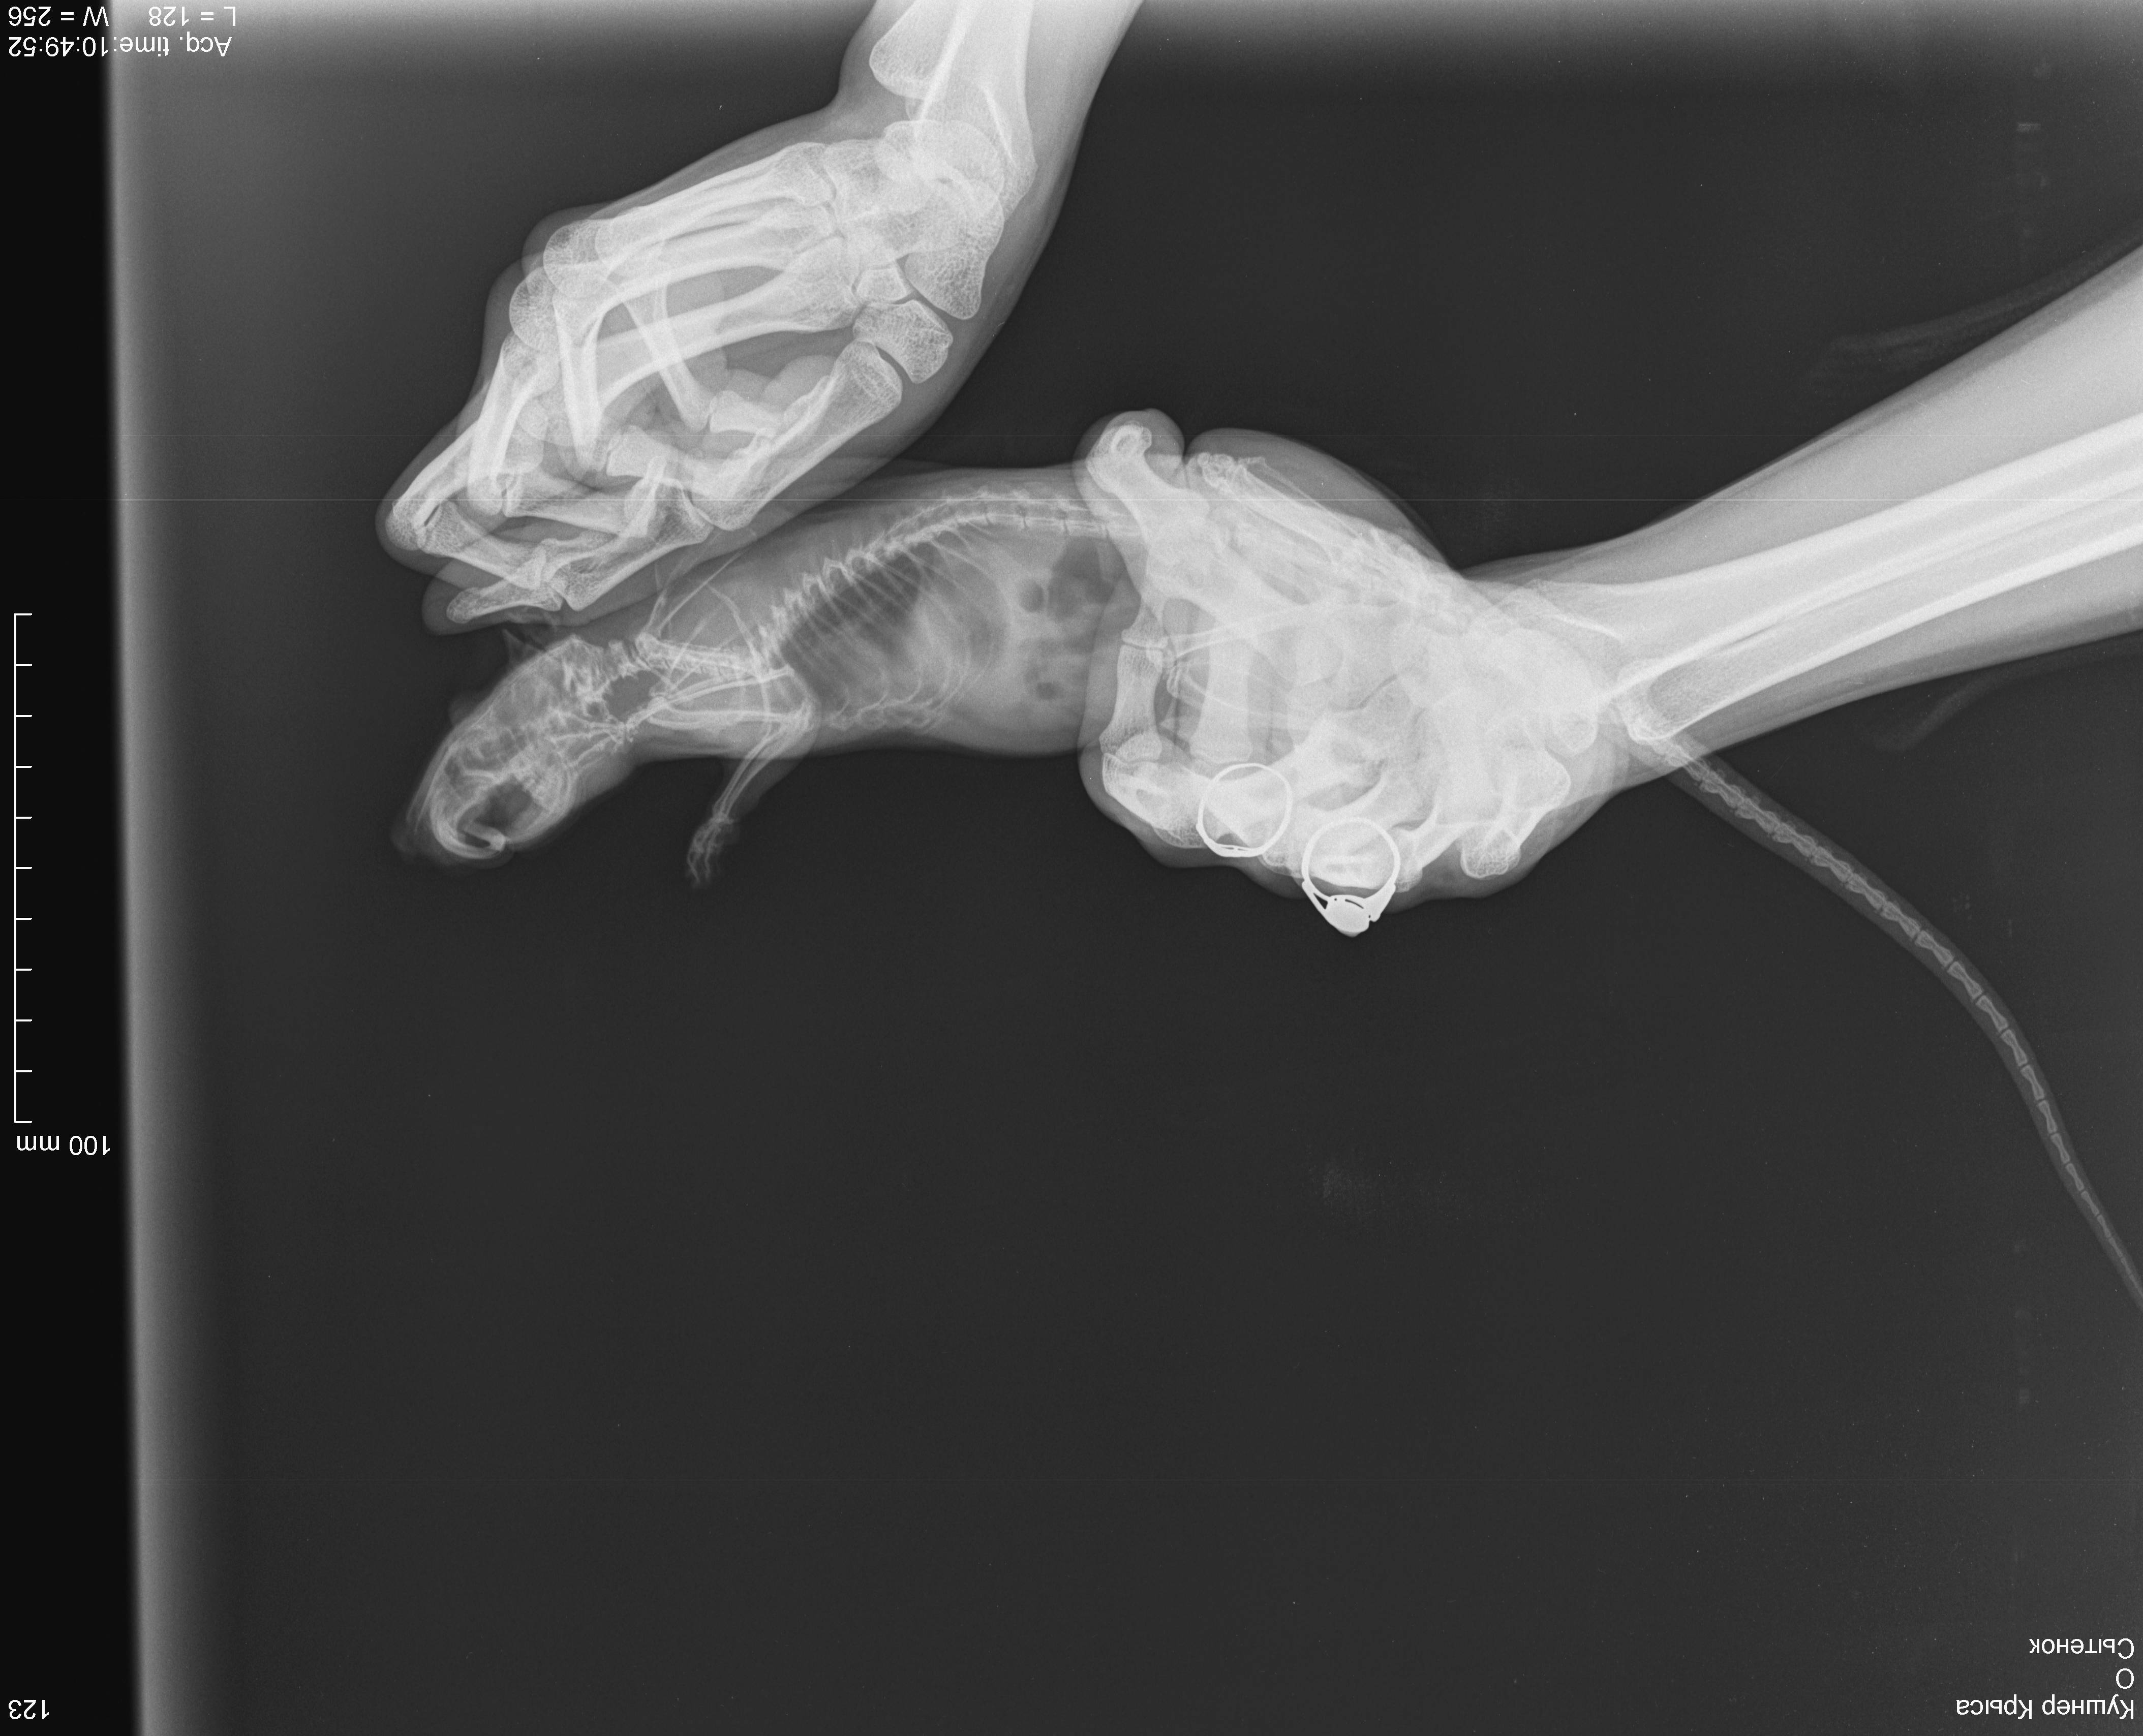

6 декабря свозила к ветеринару, послушали - услышали хрипы, больше слева, сделали рентген, врач сказала, что вероятнее всего пневмония, назначила синулокс 0,15мл в/м 1 раз в день, катозал 0,3мл 1 раз в день. По-моему стало немного получше, начал умываться. Дома пару раз пытался попить, но такое ощущение, словно захлебываться начинает и перестает, стал незначительно активнее. 8,9 декабря возила его на оксигенотерапию по 1 разу по 20минут, в состоянии особо изменения не заметила. 10 числа ближе к вечеру - крыса сидит на одном место, тяжело дышит, дышит боками, хрипы более выраженные, голова опущена вниз, беспокойный, в руки не дается. Повезла к другому врачу (рабочее время моего закончилось) - сказал, что вероятнее всего отёк легких, сделал инъекцию дексаметазона 0,05мл в/м. Спросила про диуретики, сказала, что не надо, так как дексаметазон будет выполнять эту функцию в том числе.

Отметил, что если не поможет, то наварное ничего уже не поможет. Сегодня, 11 числа, стало незначительно лучше, поехала к своему врачу, она была на выезде, приняла другая девушка, сказала что не отёк, т.к. хрипы должны быть другие. Назначила ингаляции беродуала и соответственно продолжать назначенную терапию. Я не знаю, продолжать ли терапию, или её стоит поменять или я только мучаю крысу и ей врят ли уже помогут. Есть ли смысл покупать беродуал? Посмотрите на снимки, пожалуйста, действительно ли пневмония, а не онко? В прямой проекции видно затемнение в проекции шейных позвонков, но на боковой его не вижу, врачи сказали, что это надгортанник

, хочется быть уверенной, что не какое-нибудь инородное тело.